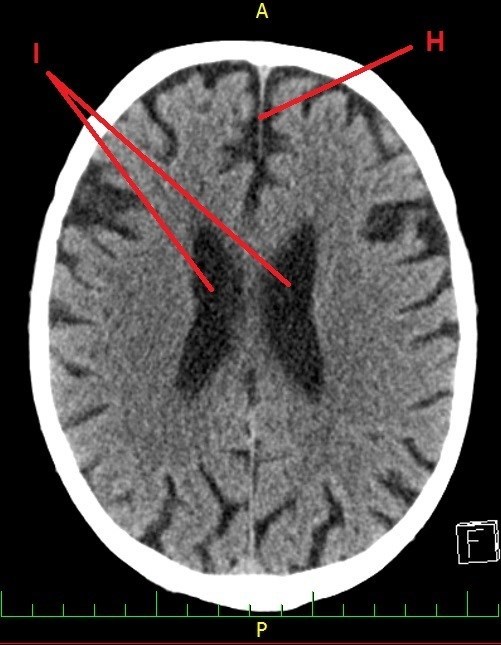

A dál co potřebujete k získání finálních souřadnic? Trocha z té zdravotnické praxe. Správný geokačer má silně vyvinutý smysl pro všímání si detailů, skrytých souvislostí a tak podobně. Princip je jednoduchý. Nepůjde o žádnou kdoví jak složitou matematickou šifru s IT podtextem. V budoucích několika minutách, hodinách či dnech se z Vás stanou radiologové (lékaři zabývající se zobrazovacími technikami) a anatomové. Tak Vás jistě nepřekvapí několik obrázků, na kterých bude vyznačen útvar, který musíte poznat a latinsky (pokud jiným jazykem, tak Vás na to upozorním) pojmenovat. Myslím, že vše bude jasné. Tak jdeme na to…

H - počet písmen v názvu útvaru (latinsky, 2 slova)

I - počet písmen v názvu útvaru (latinsky, 2 slova, plural)